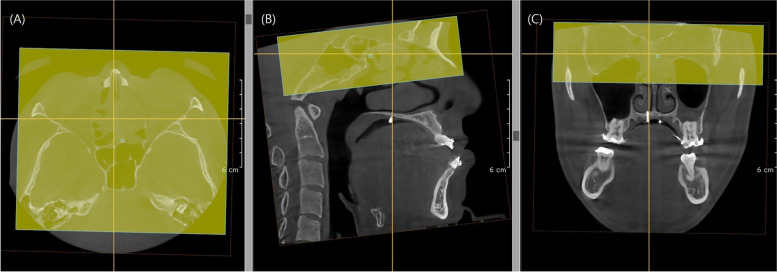

Methods: This retrospective cohort study investigated patients who underwent mandibular setback surgery using bilateral sagittal split ramus osteotomy. Three-dimensional CT scans were taken at three different time points. Evaluation of the postoperative stability involved measuring changes in the x, y, and z axes as well as roll and yaw rotations of the mandible at specific landmarks (B point, mental foramen) on 3D CT scans obtained immediately after surgery and 6-12 months postoperatively. They were categorized into four groups based on bilateral mandibular height asymmetry through Asymmetry index (AI). The one-way ANOVA was implemented to compare the intergroup differences and Tukey's post hoc test was employed. Additionally, the Pearson correlation coefficient was also calculated.